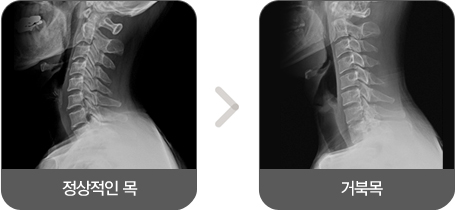

C자 형태가 아닌 일자 형태의 수직으로 변형된 상태를 일자목증후군 또는 거북목증후군 이라고 합니다. 목은 7개의 척추와 그 척추를 연결해주고 있는 디스크와 수많은 근육과 인대로 구성되어 있습니다.

이러한 경추(목뼈)는 옆에서 보았을 때 C자 형태로 척추의 정상적인 커브를 나타내고 있어야 하는데 일자 형태의 수직으로 변형된 상태를 일자목증후군 또는 거북목증후군 이라고 합니다.

경추의 C자 커브는 스프링처럼 충격을 분산시키는 역할을 하는데 일자목이 되면 충격 완화 능력이 현저히 떨어져 외부 충격이 척추에 고스란히 전달되어 디스크 퇴행을 촉발하게 되어 목디스크가 생기거나 경추에 퇴행성 질환이 생길 수 있습니다.